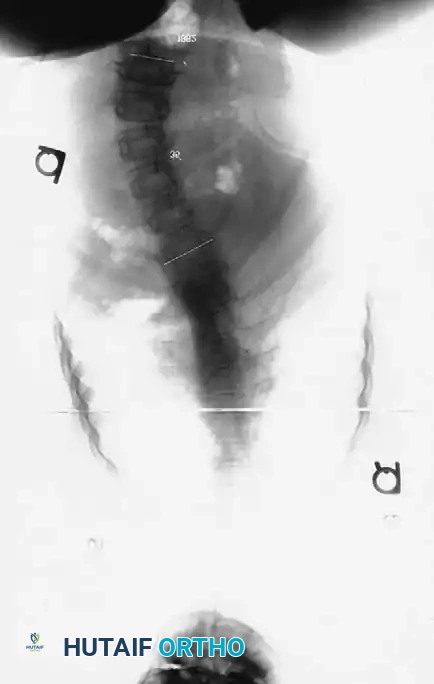

Associated Surgical & Radiographic Imaging

Hutaifortho's Orthopaedic Diagram